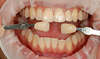

Les techniques d’éclaircissement dentaire par gouttière

La procédure consiste à appliquer un gel sur les dents grâce une gouttière souple